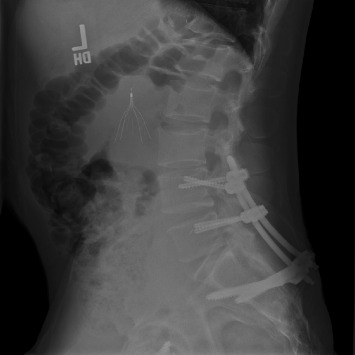

导读:脊柱骨盆分离是一种毁灭性的损伤,由于其复杂性和低发病率,仍然难以管理。腰椎骨盆固定是一种传统的治疗选择,采用开放入路。然而,在严重的多发创伤患者中,开放式固定与大量失血和感染风险相关。技术的进步使得这种手术可以经皮进行。因此,我们评估了接受开放式腰骨盆固定和接受经皮腰骨盆固定的患者之间的结果。方法:回顾性分析2012年至2024年接受开放或经皮腰骨盆固定治疗脊柱骨盆分离的患者。采用AOSpine分类系统对所有骨折进行分类。分析患者人口统计学、临床和手术结果。结果:48例脊柱骨盆分离患者纳入最终分析,其中21例接受开放式腰骨盆固定,27例接受经皮腰骨盆固定。两组患者术前特征和人口统计学相似。经皮组出血量明显减少(82 mL vs. 679 mL;P < 0.01),手术时间较短(168∶284 min;P < 0.01),手术部位感染较少(0比4;p=0.03),降低了手术室成本(35,097美元vs. 23,743美元;P =0.01),但盆腔前环损伤率较高(63% vs. 19%;p = 0.003)。两组患者的住院时间(p=0.63)和随访时间(p=0.64)均无统计学差异。结论:我们的研究结果表明,经皮腰盆腔内固定术是一种具有吸引力的微创且时间短的治疗脊柱盆腔分离的方法,而且不会增加发病率。

Introduction: Spinopelvic dissociation is a devastating injury that remains difficult to manage due to its complexity and low incidence. Lumbopelvic fixation is a treatment option traditionally performed with an open approach. However, open fixation is associated with substantial blood loss and infection risk in critical polytrauma patients. Technological advancements have enabled this procedure to be performed percutaneously. Thus, we evaluate outcomes between patients receiving open lumbopelvic fixation and those receiving percutaneous lumbopelvic fixation. Methods: A retrospective review was conducted of patients undergoing either open or percutaneous lumbopelvic fixation for spinopelvic dissociation from 2012 to 2024. The AOSpine classification system was used to classify all fractures. Patient demographic, clinical, and operative outcomes were analyzed. Results: 48 patients with spinopelvic dissociation were included in the final analysis, with 21 receiving open lumbopelvic fixation and 27 receiving percutaneous lumbopelvic fixation. Preoperative characteristics and demographics were similar between the two groups. The percutaneous group demonstrated significantly reduced blood loss (82 vs. 679 mL; p < 0.01), shorter operative time (168 vs. 284 min; p < 0.01), fewer surgical site infections (0 vs. 4; p=0.03), and reduced OR cost ($35,097 vs. $23,743; p=0.01) but had a higher rate of anterior pelvic ring injuries (63% vs. 19%; p=0.003). There was no significant difference in length of stay (p=0.63) or length of follow-up (p=0.64). Conclusion: Our findings suggest that percutaneous lumbopelvic fixation offers an attractive less invasive and shorter procedure to treat spinopelvic dissociation without added morbidity.